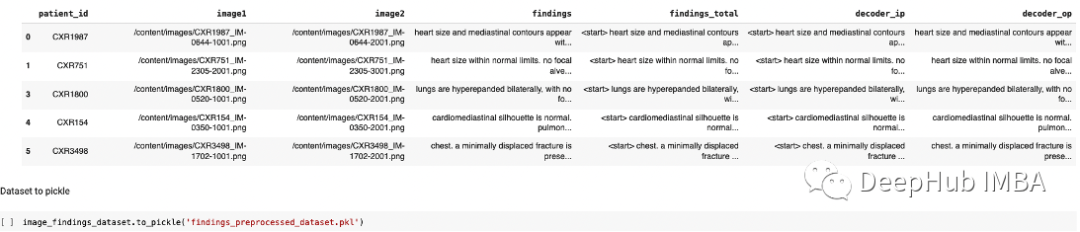

使用XML库,我们从每个患者XML报告中提取“发现”、图像路径和患者id信息,并与它们形成一个数据集。

为了捕获大部分信息,我们将两个图像的输入提供给模型,规则如下

如果患者有一张与报告相关的 X 射线图像,我们将相同的图像复制两次作为 image1 和 image2。

如果患者有两张与报告相关的 X 射线图像,我们将第一张图像做为 image1,第二张做为 image2。

如果患者有两个以上的 X 射线与报告相关联,我们随机选择 2 个 作为 image1 和 image2。

针对于“发现列”的数据处理

在发现列中大约有13%的空值。我们将删除在结果列中具有空值的行,因为没法用随机的结果填充空值。并将其转换为小写,删除垃圾词